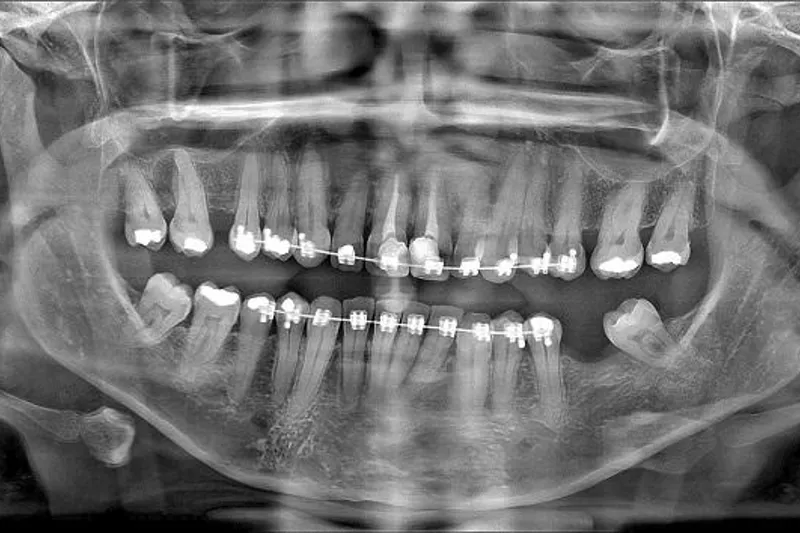

Panoramaoptagelse bør overvejes ved mistanke om kæbefraktur. Frakturer i underkæben diagnosticeres relativt sikkert på panoramaoptagelser. CBCT kan overvejes ved mistanke om kæbefraktur i overkæben og/eller mellemansigtet. CBCT kan også afsløre eventuelle tandfrakturer med relativt stor sikkerhed, forudsat at der ikke i strålefeltet er artefaktdannende genstande som fx metalkroner, stifter, rodfyldninger eller ortodontisk apparatur.

Igen skal du være opmærksom på, at rodfrakturer er vanskelige at diagnosticere på CBCT, hvis der er artefakter.

Der vil sjældent være indikation for CBCT til rene luksationsskader; men hvis der af anden årsag tages CBCT, kan optagelsen afsløre eventuelle luksationer med relativt stor sikkerhed, forudsat at der ikke i strålefeltet er ting, der kan give anledning til artefakter på optagelsen.